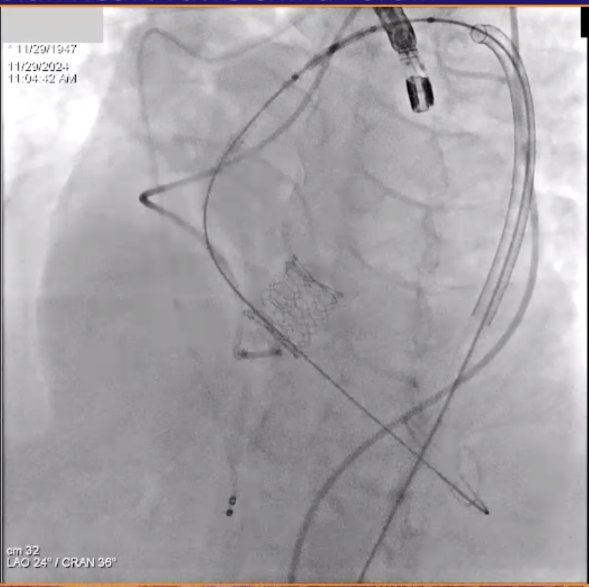

患者男性,77岁,三叶瓣。主动脉瓣重度狭窄,术前平均跨瓣压差48mmHg,峰值流速4.6m/s。瓣环及瓣叶钙化,瓣环面积径23.4mm。左冠高度11.8mm,右冠高度16.5mm。外周入路未见明显钙化,内径尚可。

手术经右侧股动脉入路,使用19mm球囊预扩,术中植入23# RENATUS®球扩式经导管主动脉瓣。输送器顺利通过,瓣膜精准释放,术后即刻平均跨瓣压差由48mmHg降至5mmHg,术后峰值流速由4.6m/s降至2.0m/s。瓣膜释放位置理想、形态及功能良好,无外周血管损伤,术后无明显瓣中及瓣周反流等并发症。

术中造影